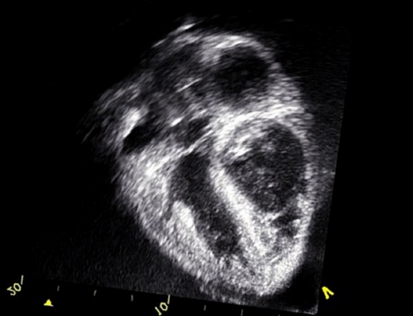

Znanstvena revija The Lancet je objavila rezultate zaključka desetletne epidemiološke raziskave o vplivu kakovosti zraka na srčnožilne bolezni, opravljene na 6000 preiskovancih. Izpostavljenost onesnaževalcem v zraku so za vsakega udeleženca ocenili z računalniškim modelom glede na njegov kraj bivanja. Ugotovitve so primerjali z večkratnimi meritvami depozitov kalcija v koronarnih arterijah in debelino stene skupne karotidne arterije. Omenjeni meritvi označujeta obseg ateroskleroze oziroma poapnenja žil, ki je glavni povzročitelj ishemične srčne bolezni.

Ugotovili so, da je izpostavljenost onesnaženemu zraku statistično povezana s pospešenim razvojem ateroskleroze. K temu najbolj prispevajo prašni delci s premerom manj kot 2,5 mikrometra ter dušikov oksid in dioksid. 20-odstotno razliko v hitrosti nastanka ateroskleroze tako povzroči povečanje koncentracije najmanjših prašnih delcev za 5 µg/m3 ali pa vsakih 35 molekul dušikovih oksidov na milijon delcev v zraku.